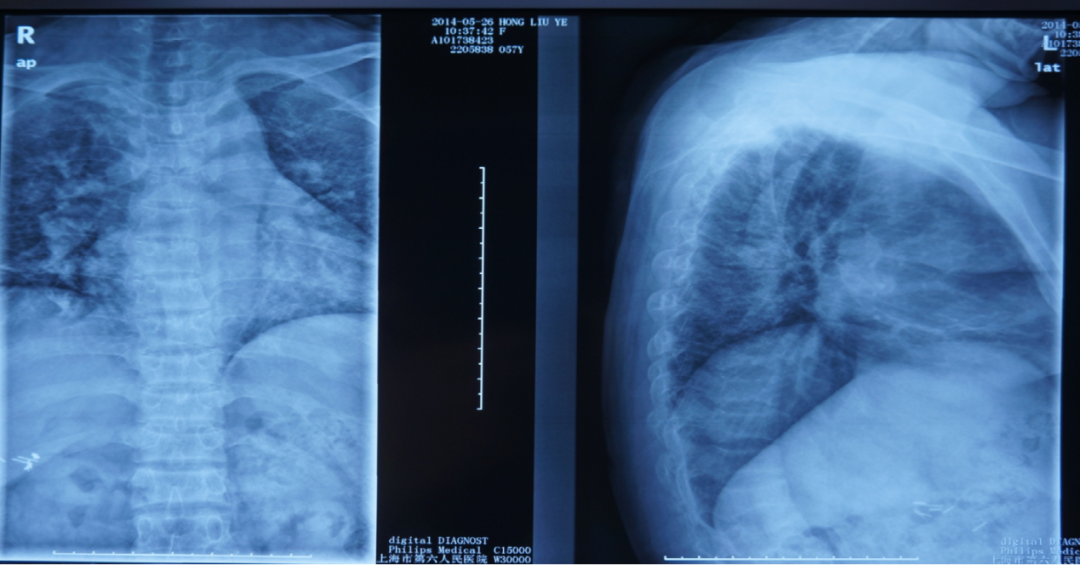

2、利用X线平片发现椎体压缩性骨折(每个医院包括社区均有):

常规进行X线胸腰椎正侧位摄片漏诊率高,患病率高(上海社区60岁以上17%,建议对50岁以上腰背部疼痛者常规摄片,及早发现椎体骨折。

二、骨质疏松症如何进行影像学检查

X线平片是检出脆性骨折,特别是胸、腰椎压缩性骨折的首选方法。常规胸、腰椎X线侧位摄片的范围应分别包括胸4至腰1和胸12至腰5椎体,基于胸、腰椎侧位X线影像并采用Genant目视半定量判定方法,椎体压缩性骨折的程度分类如下:

X线检查:胸腰椎多发压缩性骨折伴骨质疏松。

X线检查:L2压缩性骨折椎体骨质疏松,头颅未见异常。